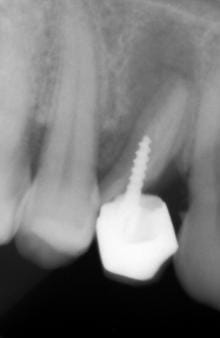

record battu?

Screw glugm0 - Eugenol

Ou est-ce que ça s'achète vos couronnes à visser directement dans les trous des racines ? Il y a plusieurs tailles ?

alors là allen je dis bravo, je te discerne le 1ER PRIX PROVISOIRE SECTION RADIO,les larmes m'en viennent aux yeux, excuse je suis très émotif---------------------------------------------il y aura un résultat trimestriel , donc pr le 1er, au 1ER AVRIL avec comme récompense un envoi, autorisé par les eugénoliens, suite à un vote dèmocratique bien sur(cela changeras leurs habitudes), a la cnsd ,l' ujcd et publication souhaitée ds l'indépendantaire, nous éviterons la sécu pour ne pas perdre l'augmentation du joli mois de mai tout en gardant celle de l'urssaf:que tout ceci reste entre nous --------------------------------------allez mes amis, a vos archives radios ET photos